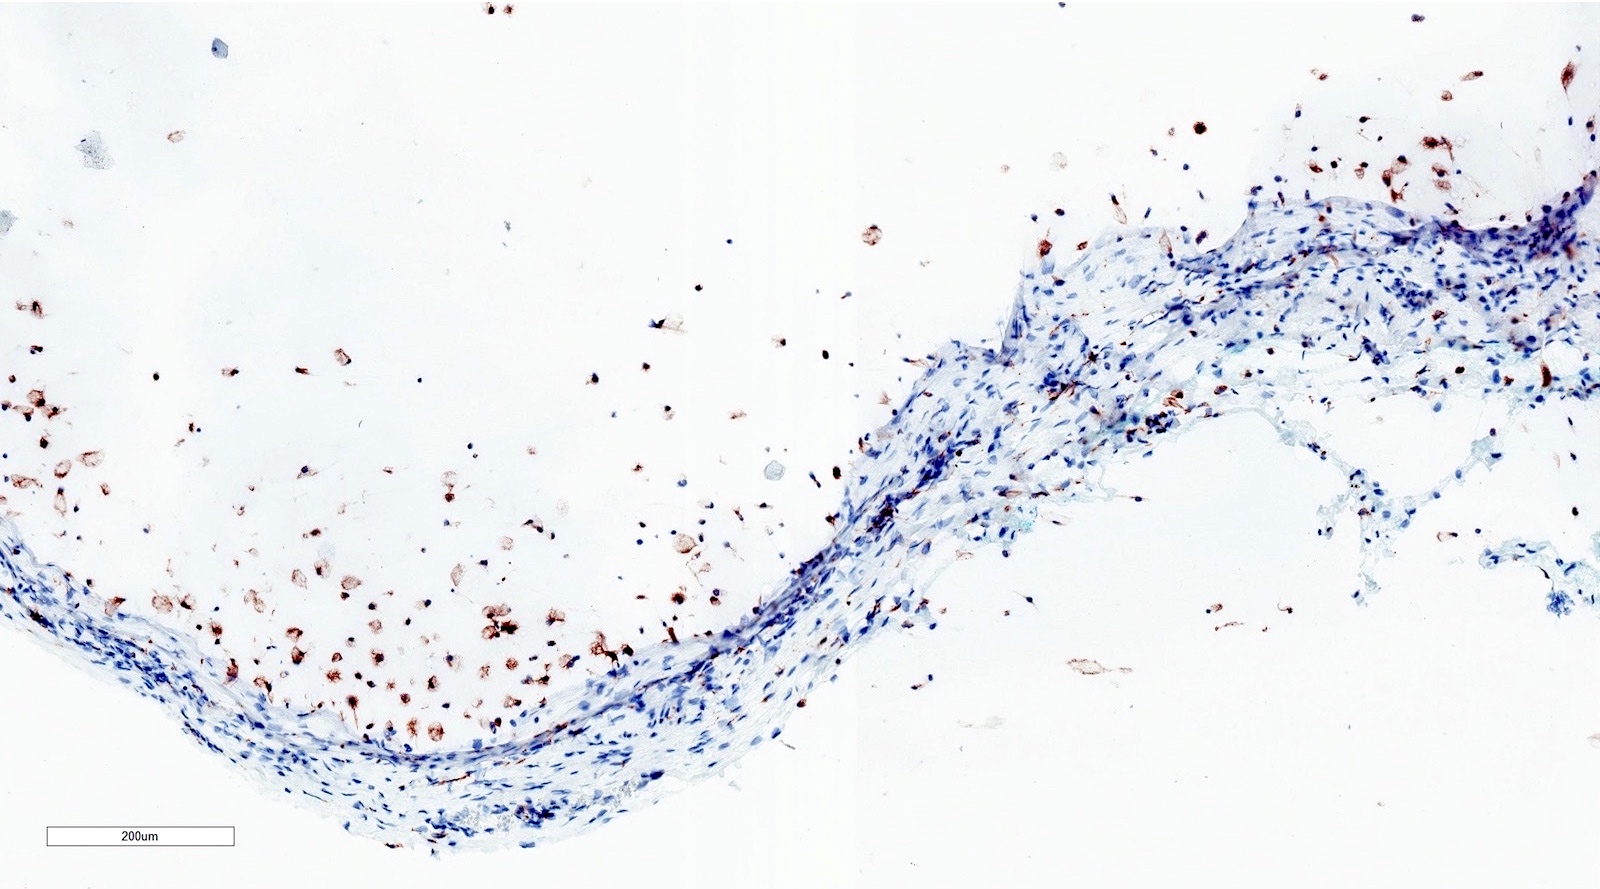

Microscopic (histologic) images

Positive stains

- Note: stains typically not needed to make the diagnosis

- CD68

- PAS-D

- Mucicarmine

- Alcian blue